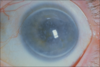

Keratoconus

vogt’s striae